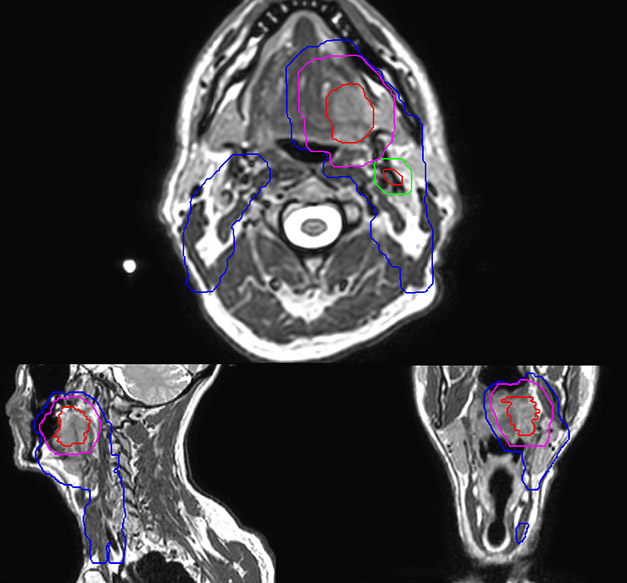

Epidermoid carcinoma of the left tongue base

The patient was diagnosed with an epidermoid carcinoma of the base of the left invading the amygdala lodge and the amygdaloglossal groove. Radiochemotherapy with curative aim was prescribed with a dose of 70 Gy for the tumor, 66 Gy on the suspicious nodes and 56 Gy on the elective drainage areas - in 33 fractions.

T2W 3D, 3D STIR and mDIXON MRI scans.

Comparison of CT simulation scan (left) and T2W 3D MRI (right)

MR-based target contouring on 3D T2W TSE in transversal, sagittal and coronal planes.

Personalized VMAT dose planned in Philips Pinnacle.